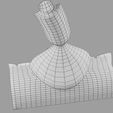

神经肌肉接头示意图